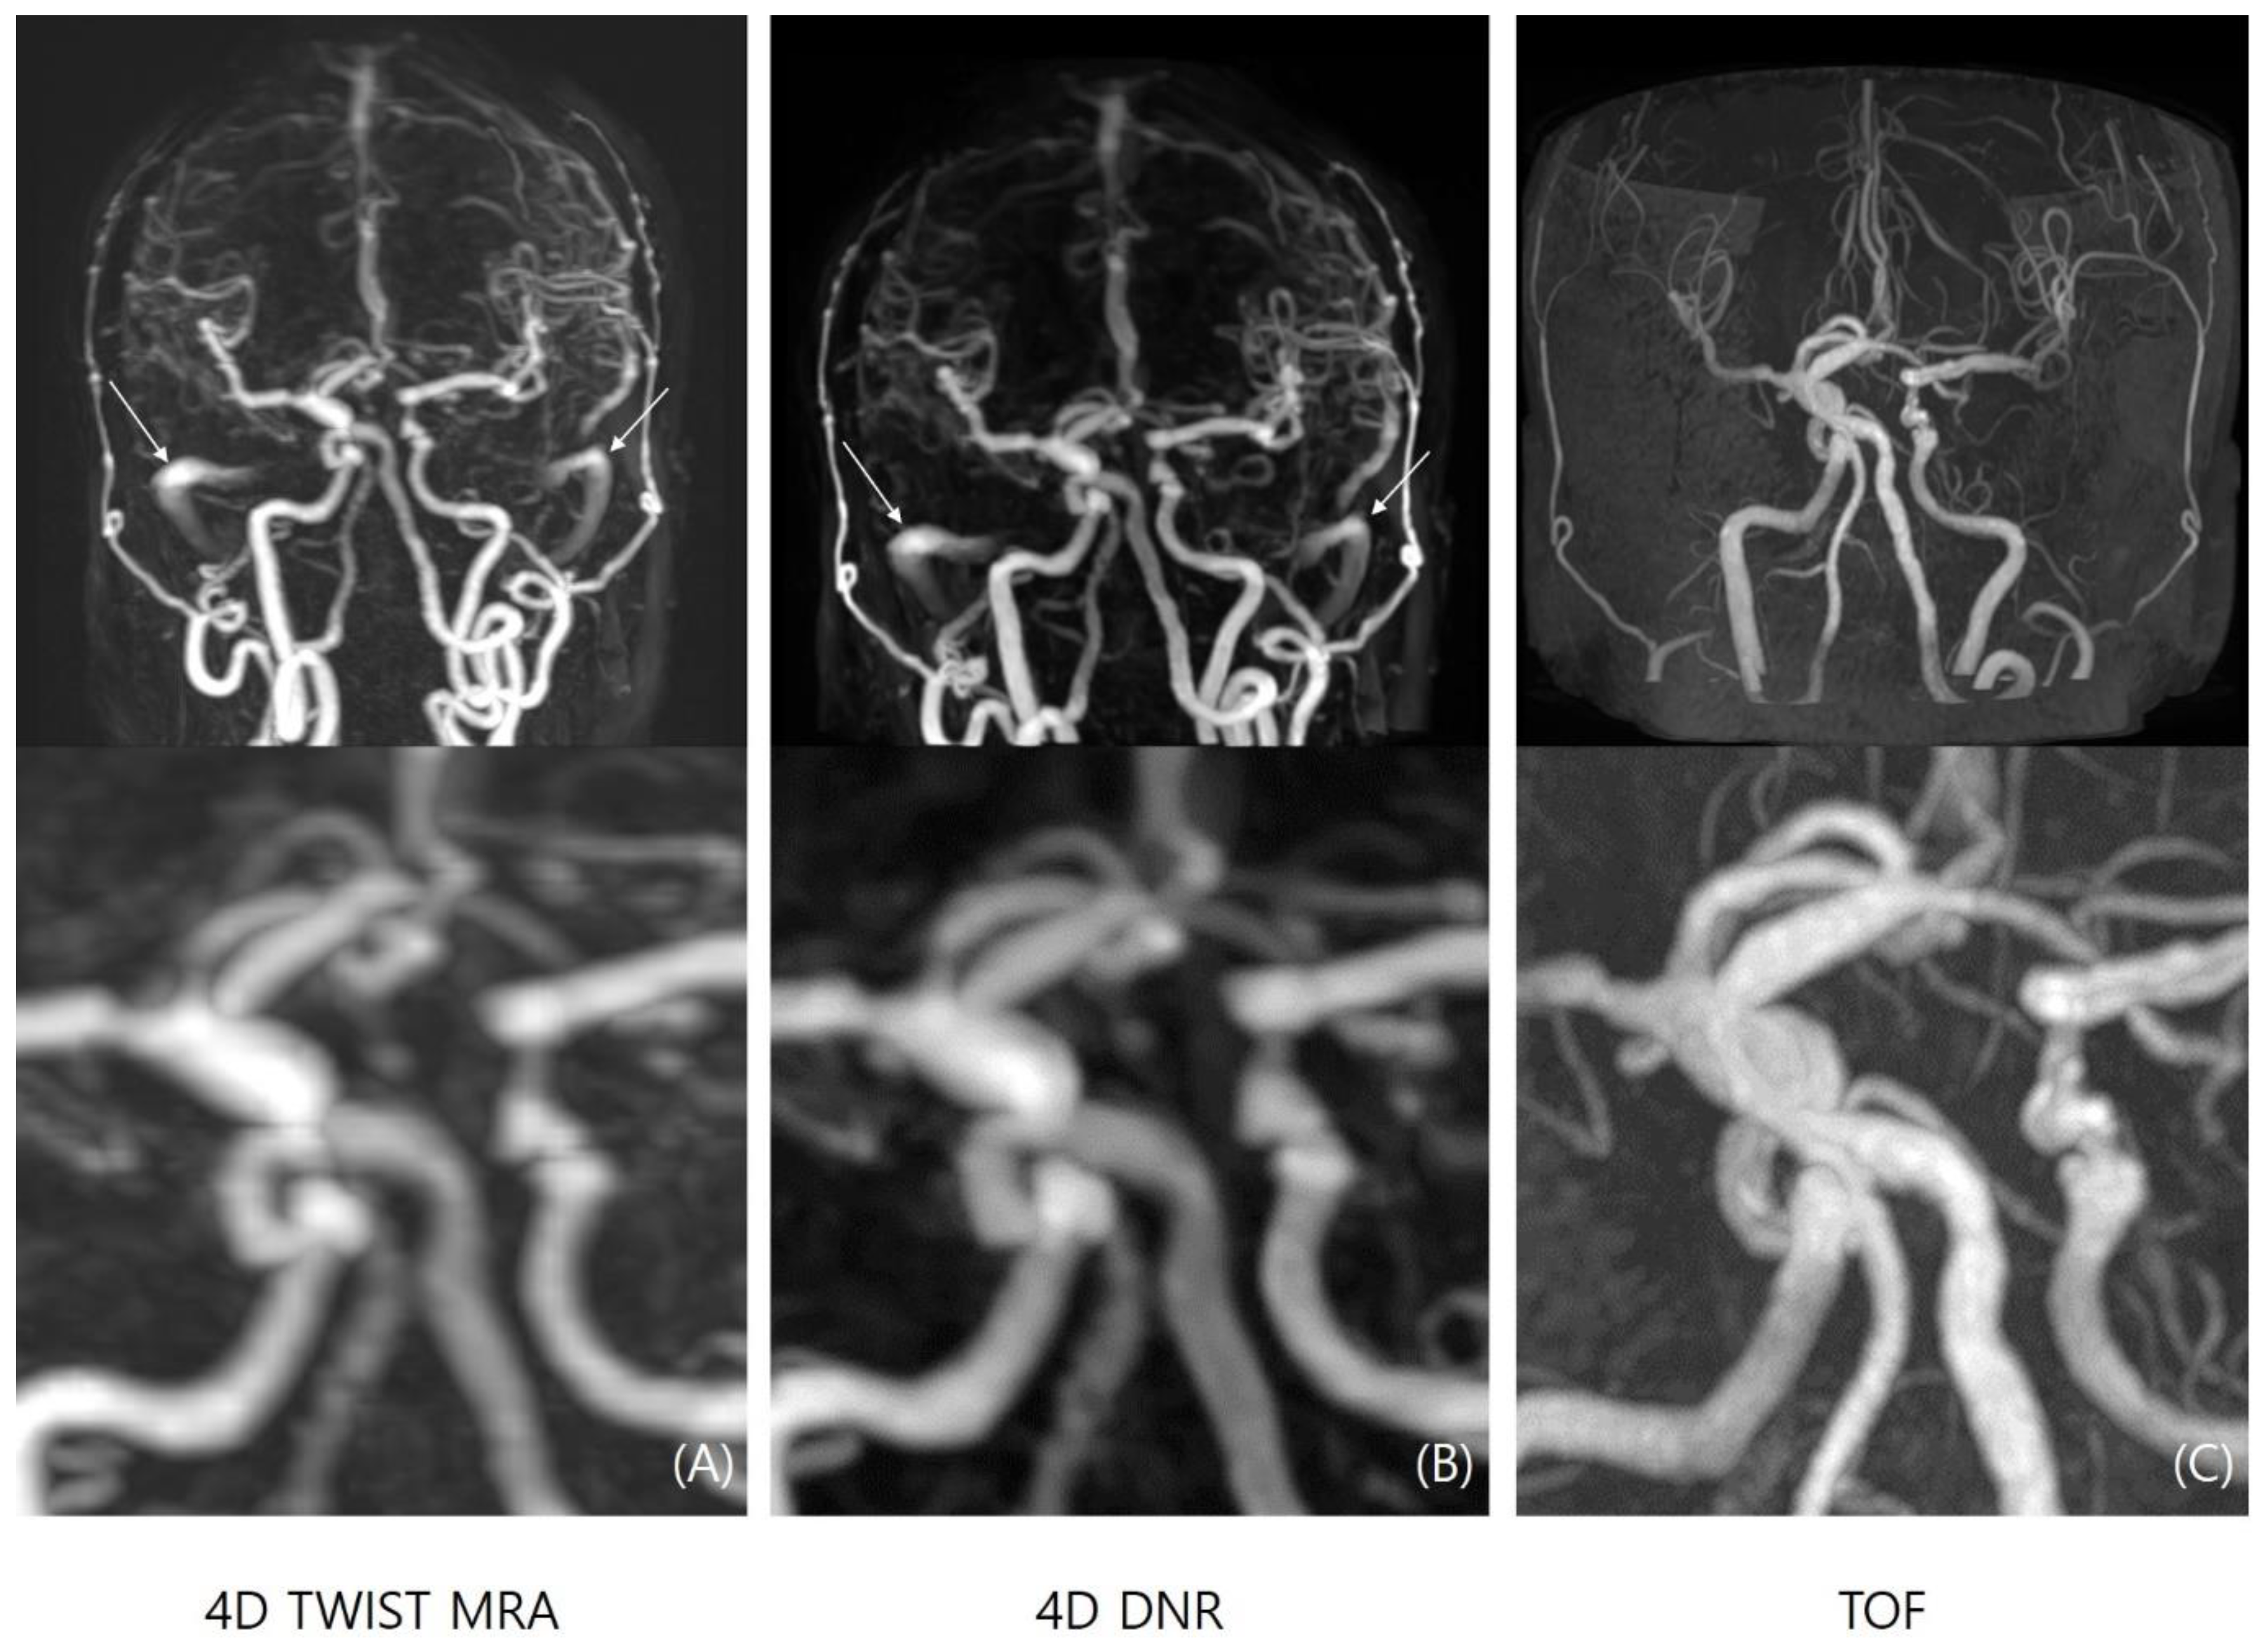

Image Quality Comparison between TOF-MRA, 4D-TWIST-MRA, and 4D-DNR

3.1. Image Quality Assessment

3.2. Aneurysm Detection